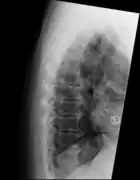

"Melted candle wax" appearance of calcification and ossification in diffuse idiopathic skeletal hyperostosis (DISH). Note the preponderance on the patient's left side (right side of image).